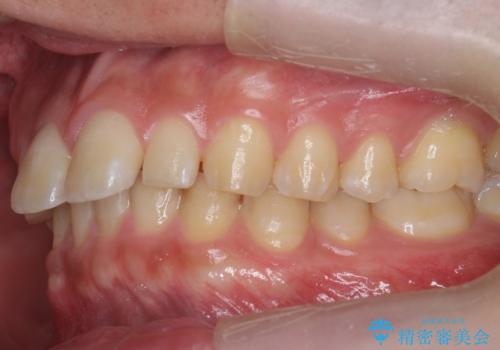

- インビザライン(マウスピース矯正)

- 治療期間

- 11ヶ月

矯正治療で1番目の歯を寄せて2番目の歯はセラミックで形をととのえています。

- 矯正治療費 93.5万円 (セラミック代別)費用は治療当時の料金となります